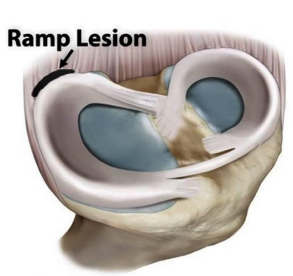

Ci possono essere lesioni che associano alla Sindrome da conflitto/impingement della caviglia?

Le lesioni associate in particolare ai legamenti ed alla cartilagine (vedi trattamento nella sessione specifica). In caso di lassità legametose associate ad instabilità si può associare al trattamento artroscopico una stabilizzazione legamentosa con tecnica mini-invasiva.

b) L’impingement antero-laterale si osserva a livello di un recesso sinoviale localizzato tra tre strutture ossee: tibia, fibula e astragalo; tale area anatomica è delimitata anteriormente dal legamento tibio-peroneale antero-inferiore e dal legamento peroneo-astragalico anteriore, ed inferiormente dal legamento peroneo-calcaneale. La sindrome è caratterizzata da dolore cronico in sede laterale esacerbato durante l’eversione o la dorsiflessione del piede, e dal salto su un piede. L’esame clinico documenta dolore nella regione antero-laterale del piede e tumefazione nelle fasi più avanzate. L’impingement può essere causato da un solo trauma o da microtraumi ripetuti. La distorsione di caviglia è universalmente considerata uno dei più comuni traumi osservati; si ha soprattutto durante l’attività sportiva ed è più frequente soprattutto nei giocatori di basket e nei calciatori, e nella maggior parte dei casi si tratta di pazienti che hanno meno di 35 anni. Nell’85% dei casi, l’evento traumatico si ha in inversione e coinvolge il complesso legamentoso laterale, nel quale il legamento più facilmente colpito è il legamento peroneo-astragalico anteriore.

Il trattamento conservativo porta alla guarigione senza complicanze nella maggior parte dei casi; tuttavia si è stimato che circa il 3% delle distorsioni di caviglia può portare ad una sindrome da impingement antero-laterale. Un trauma in inversione con almeno una lesione parziale del legamento talo-fibulare anteriore può determinare un danno con conseguente reazione infiammatoria della sinovia a livello dell’interlinea articolare antero-laterale. In assenza di un adeguato trattamento di immobilizzazione o di riabilitazione, può aversi ipertrofia e fibrosi cicatriziale a livello della sinovia. La cronicizzazione di questi fenomeni può portare allo sviluppo di una proliferazione che si estende nel recesso antero-laterale e che causa impingement meccanico e dolore. Più raramente questa massa può determinare l’erosione della porzione antero-laterale del domo astragalico, con conseguente sviluppo di foci di condromalacia. Oltre all’ispessimento ed alla deformità cicatriziale del legamento tibio-fibulare anteriore, la RM eseguita su piani di scansione assiali e sagittali, mostra, soprattutto in presenza di versamento intra-articolare, un’intensità di segnale intermedia del tessuto sinoviale sia nelle sequenze T1 che T2 pesate . RM ed artro-RM, soprattutto in presenza di versamento intra-articolare, sono in grado di documentare sia l’ipertrofia sinoviale, causa di impingement antero-laterale, che eventuali lesioni cartilaginee, ossee e legamentose associate.